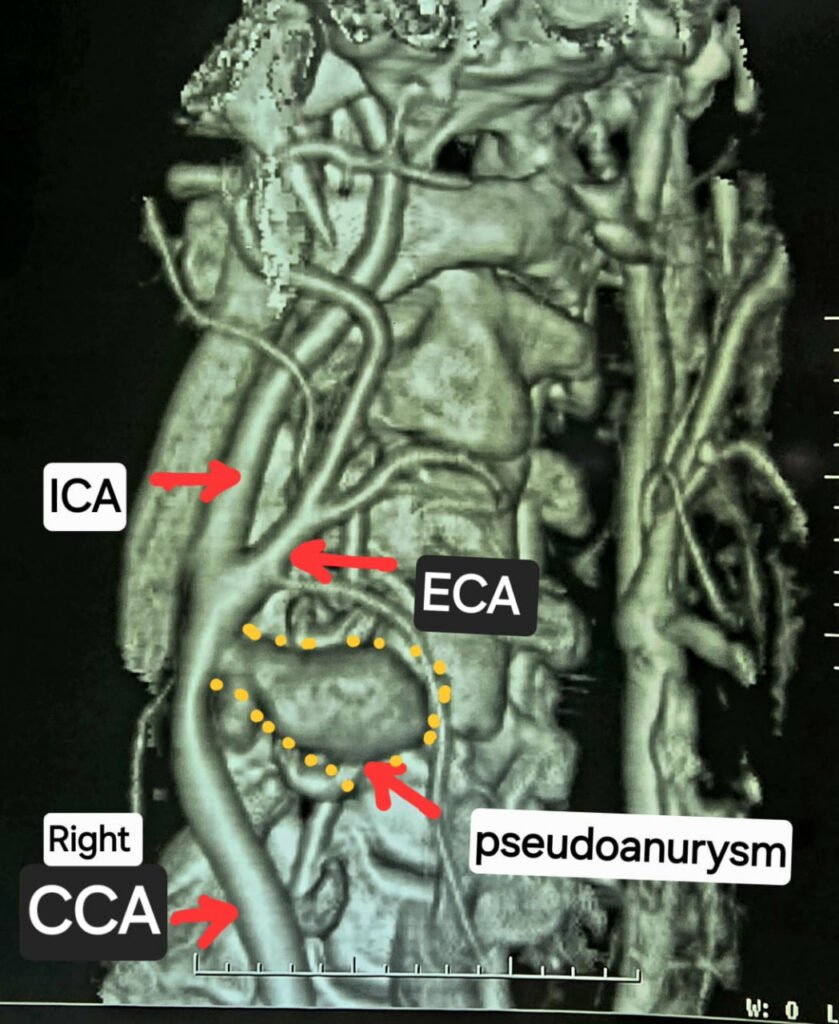

सीटी एंजियोग्राफी जाँच से पता चला दुर्लभ केस

गर्दन के नसों की सीटी एंजियोग्राफी जांच में यह चौंकाने वाला तथ्य सामने आया कि मरीज की दायीं कैरोटिड आर्टरी फट चुकी है और उसके चारों ओर गुब्बारानुमा संरचना बन गई है, जिसे कैरोटिड आर्टरी स्यूडोएन्युरिज्म (Carotid Artery Pseudoaneurysm) कहा जाता है। स्थिति की गंभीरता को देखते हुए मरीज को तत्काल हार्ट, चेस्ट एवं वैस्कुलर सर्जरी विभाग में में डॉ कृष्ण कांत साहू के पास भेजा गया।